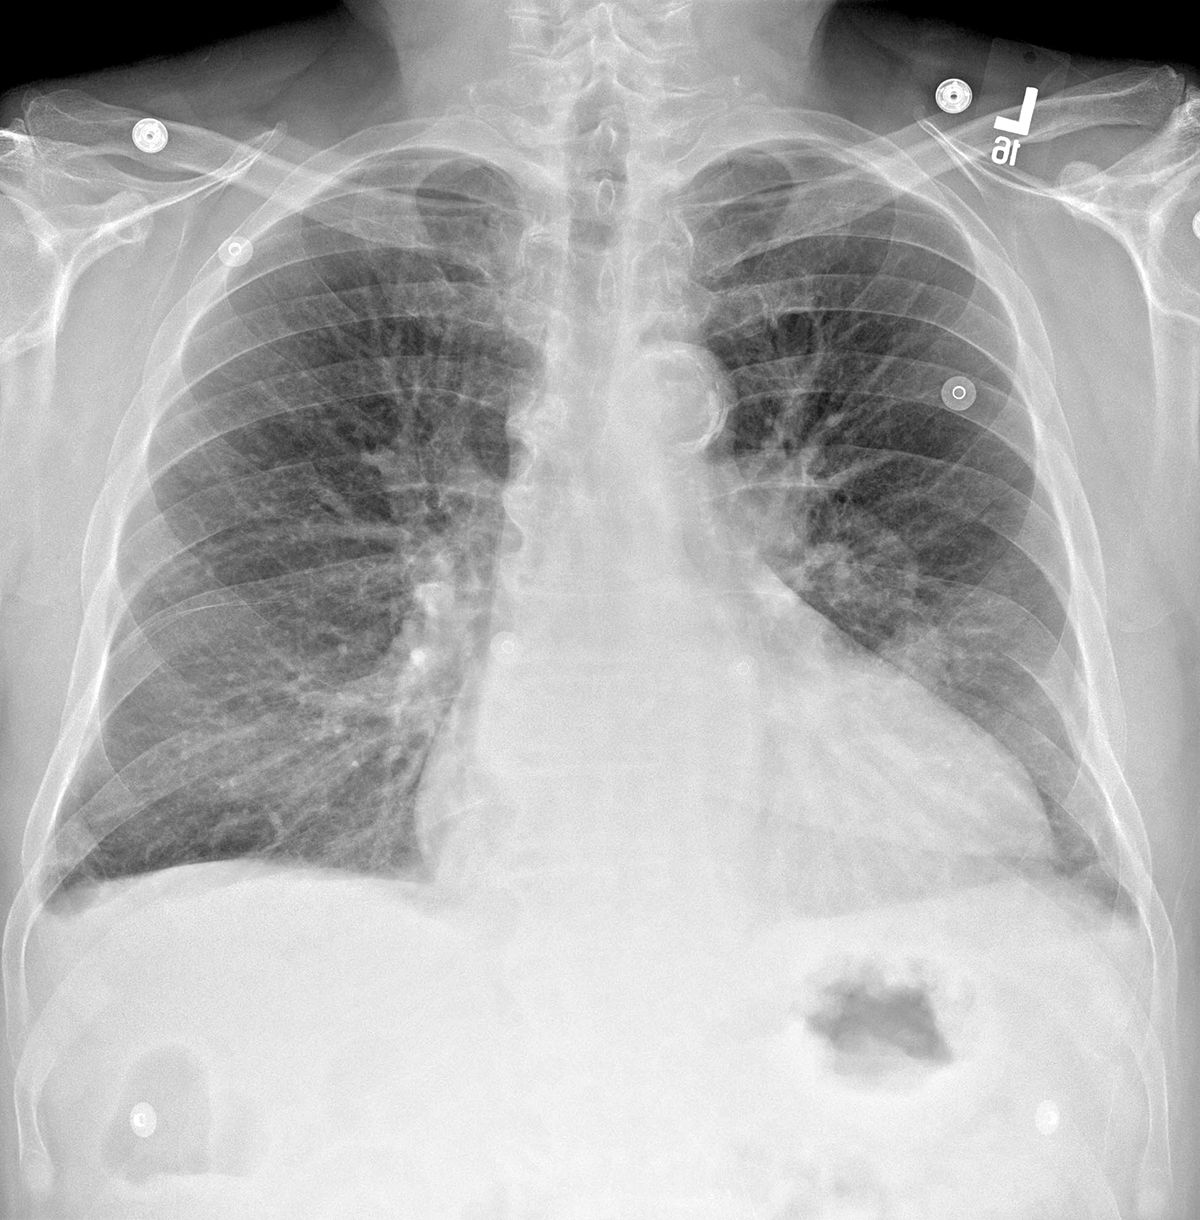

Topic 2

basic case CHF

Further Explanation: